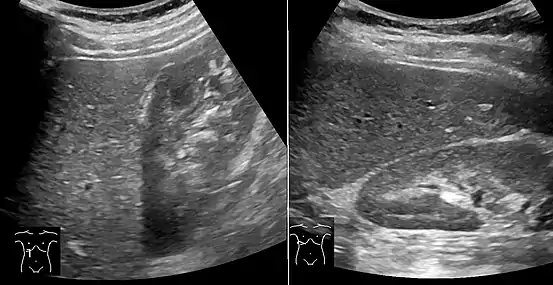

Medical imaging

On X-ray computed tomography (CT), the increased fat component will decrease the density of the liver tissue, making the image less bright. Typically the density of the spleen and liver are roughly equivalent. In steatosis, there is a difference between the density and brightness of the two organs, with the liver appearing darker.[12] On ultrasound, fat is more echogenic (capable of reflecting sound waves). The combination of liver steatosis being dark on CT and bright on ultrasound is sometimes known as the flip flop sign.

On abdominal ultrasonography, steatosis is seen as a hyperechoic liver as compared to the normal kidney.